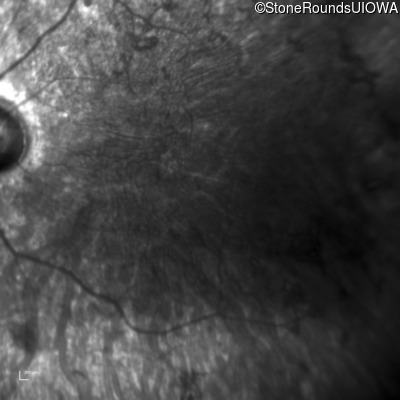

Infrared Fundus Photograph - Right - 5/180 sc

Exemplar